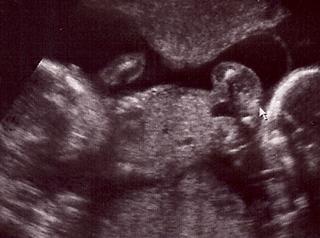

tak F. sa so mnou chysta na to d sono...tiež teraz so mnou nebol, ale vybavila som fotečky konečne...mal mi ich naskenovat, tak to idem pozriet a skusim pripojit 🙂)))))

nase bublinky s bavia medzi sebou, su otocene k sebe a netvaria sa, že nám chcu povedať že kto je kto 😀 😀 😀 ale doky povedal, že urobime coskoro to 3D, takže tam ......verim......že to vyjde .-)))))

@orsulka tak to ja beriem s rezervou - veď lax aj noe mali pekné fotečky a tiež majú dievčatká.